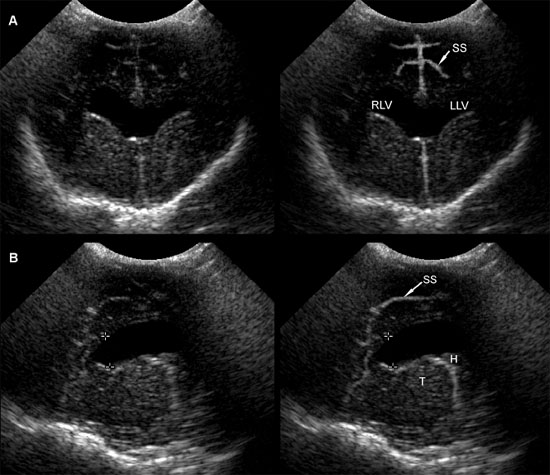

Figure 1.11. Variability in expansion of the ventricular system in hydrocephalus. Additional images from the brain of the 3-month-old Chihuahua shown in Figure 1.10 indicate that the temporal horns are minimally affected, but there is a confluence of the rostral horns. The third ventricle is not enlarged. Sonograms of another Chihuahua in Figure 1.9 show that ventriculomegaly involves the temporal horns, as well as rostral horns and central parts, and there is enlargement of the third ventricle in that dog. Midline structures remain mainly intact, however. A: Rostral transverse sonogram. B: Parasagittal sonogram. H, hippocampus; LLV, left lateral ventricle; RLV, right lateral ventricle; SS, splenial sulcus; and T, thalamus.

Several methods have been proposed for evaluating enlarged lateral ventricles on sonograms (Figure 1.10 and Table 1.1). The degree of ventriculomegaly ranges from the ventricles being only slightly enlarged to ventricles occupying most of the brain. Midline structures between the lateral ventricles are intact in some animals, but the lateral ventricles become confluent in others (Figure 1.11).

The suggested methods of measurement are not always useful (Table 1.1). Some animals may have minimal enlargement in the described planes for measurement but have greatly enlarged ventricles in other areas, such as the caudal part of the central horn and the temporal horn. The third or fourth ventricles may also be enlarged. Sonographers should be careful to record these findings, as well as any other abnormalities, including additional anomalies or masses that may be related to the ventriculomegaly.